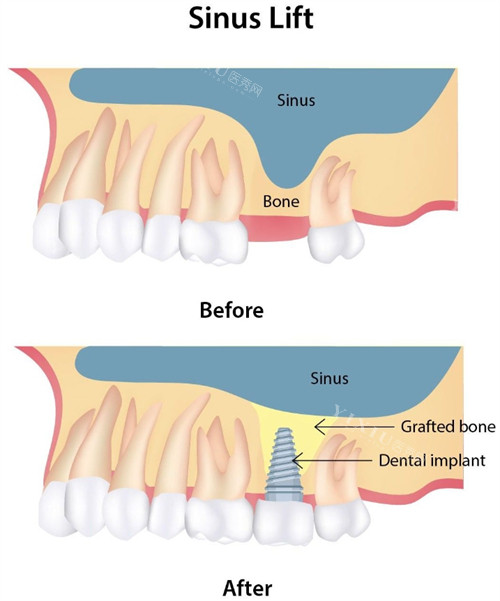

Ⅳ类骨:低密度软骨,需特殊设计

Ⅳ类骨常见于上颌后牙区,骨密度低、血供差,种植体易松动。医生建议:

种植体直径≤4mm、长度≥11mm,避免过度扩孔。

选择颈部外展或平行壁设计的种植体,利用骨皮质增强固位。

必要时采用骨挤压或上颌窦提升术,改善骨量。

Ⅳ类骨 半自攻、光滑颈圈种植体 上颌窦提升、骨挤压 上颌后牙区骨密度低